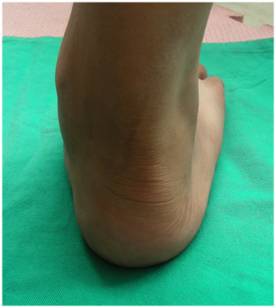

体格检查 详细而全面的体格检查,是评价扁平足畸形的严重程度;是否发生合并症;以及是否伴有关节退行性改变最基本的诊断方法。扁平足畸形通常表现为跟骨外翻,前足的内翻以及外展,有时会合并距下关节半脱位。临床检查通常以坐位、立位和行走时检查最为重要。 |

多趾征 – 从正后方观察患足,如果外侧缘看到超过两个以上的足趾,则提示多趾征阳性